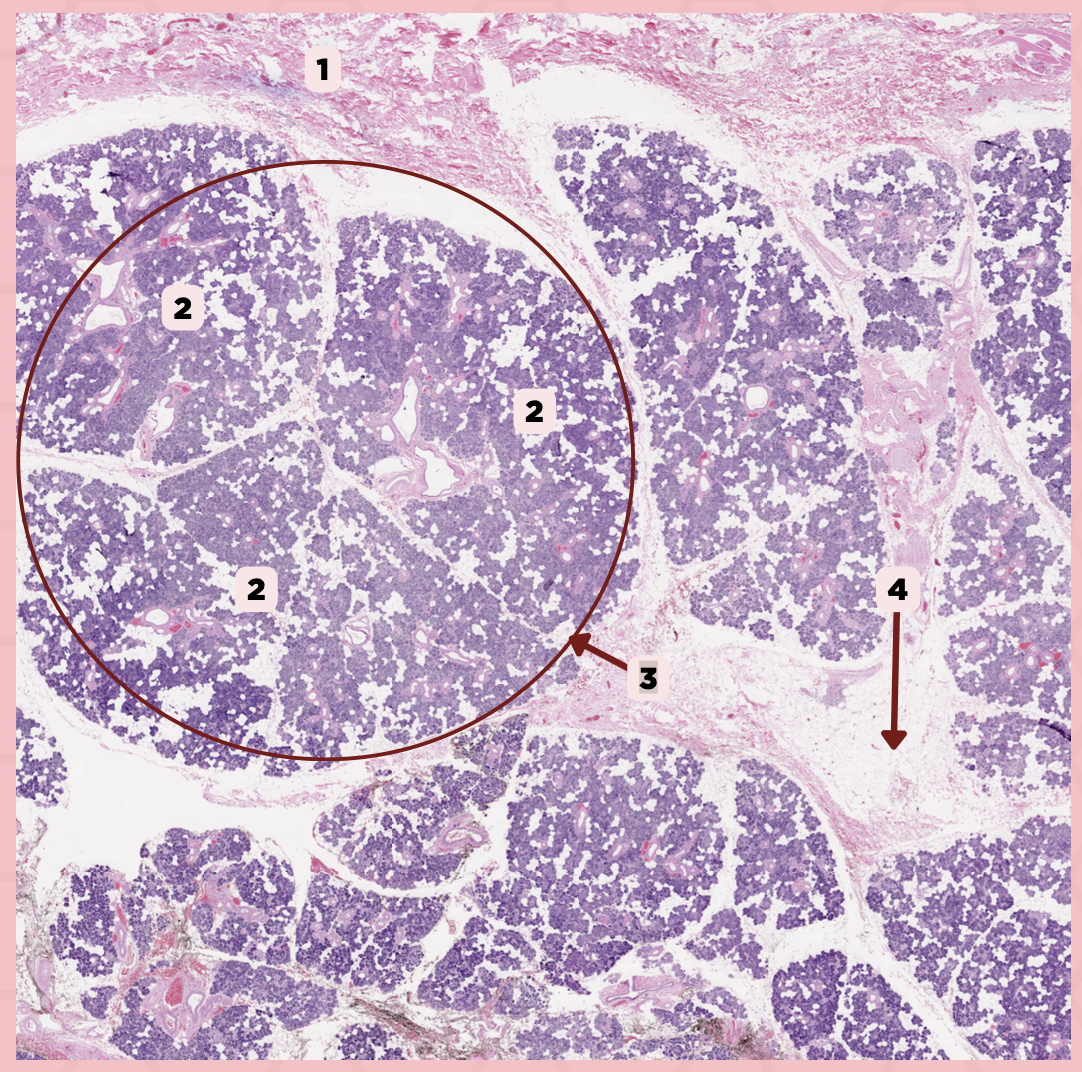

Parotid

Identify the specimen.

Capsule

Identify the structure labeled as 1.

Septa

Identify the structure labeled as 2.

Lobule

Identify the structure labeled as 3.

Lymph Node

Identify the structure labeled as 4.